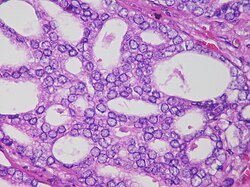

Bundan sonra prostat vəzinin biopsiyası aparılır. Bu isə prostat vəzi xərçəngi diaqnozunu təsdiq etmək üçün əsas üsul hesab edilir. Prostat vəzinin biopsiyası əksər hallarda USM nəzarəti altında aparılır. Bu zaman xüsusi alətin köməkliyi ilə düz bağırsaqdan olmaqla, hüceyrə quruluşunun müayinəsi üçün prostat vəzinin müxtəlif sahələrindən bir neçə mikroskopik (çox kiçik) tikə vəzi toxuması götürülür.